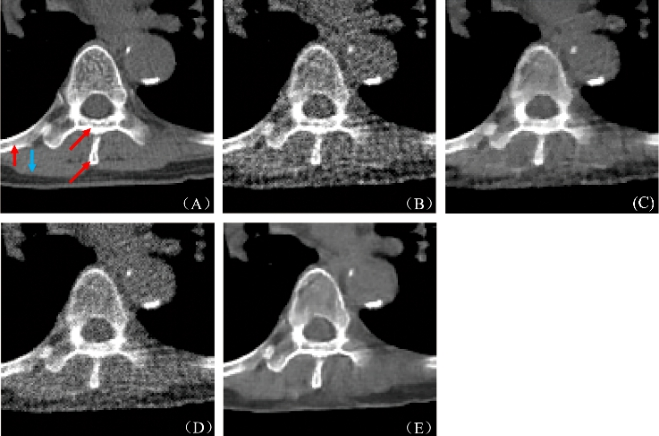

图3:图2(A)中红色标记局部区域的放大图(A) 参考图像, (B) FBP重建结果, (C) PWLS-TGV重建结果, (D) R-NLTV重建结果, (E) DD-Net重建结果